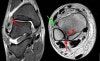

MRI : 발목 염좌(High ankle sprain)